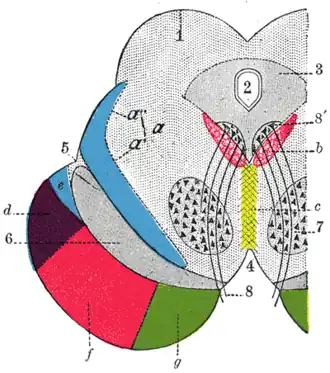

Der Großhirnschenkel zwischen Fossa interpeduncularis (4) und Sulcus lateralis (5) ventral der Substantia nigra (6) führt die corticobulbären und corticospinalen (f, Pyramidenbahn) Fasern sowie daneben medial (g) und lateral (d) corticopontine Fasern langer absteigender Bahnen.

Lange aufsteigende Bahnen sind der Lemniscus medialis (a’, e) und der Lemniscus lateralis (a’), zu den Kerngebieten der Mittelhirnhaube (Tegmentum mesencephali) zählen der Nucleus ruber (7) und Ursprungskerne (8’) des Nervus oculomotorius (8).